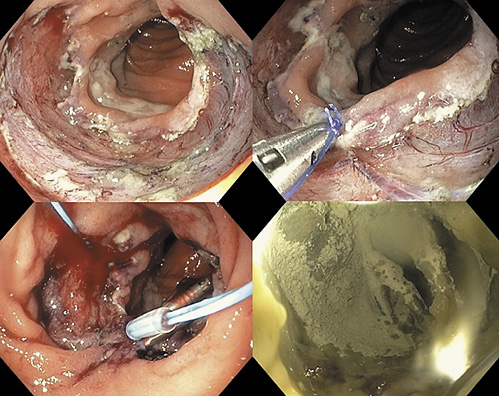

Besides the high-risk of adverse events during the procedure, duodenal ESD has a high risk of late adverse events, due to the exposure of the muscular layer to biliary and pancreatic juices. Therefore, we attempted to close the defect by the string-clip suturing method [2]. First, a clip with a string was passed into the endoscopic channel and displaced in the anal side of the ulcer. Then, a second clip was hooked in the string and displaced in the opposite (oral) side, and the two clips were gathered by pulling the string. After approaching the two margins, we tried to achieve the complete closure. Unfortunately, we were only able to close half of the defect, due to the poor mobility of the duodenum. In order to offer some protection to the muscle layer, we decided to prophylactically apply hemospray in the open area of the ulcer (Fig. 3).

The lesion measured 60 × 40 mm and the procedure took 150 min. The patient was admitted to the hospital and stayed there for 1 week to address possible late adverse events related to the inability of complete closure of the defect, with double-dose proton pump inhibitor, that maintained for 8 weeks, and a stepwise progression to a normal diet. No late adverse events were observed.

Histological evaluation showed a high-grade dysplastic lesion, with free margins. Follow-up endoscopy showed a scar with some regenerative tissue; biopsies confirmed the absence of dysplasia.